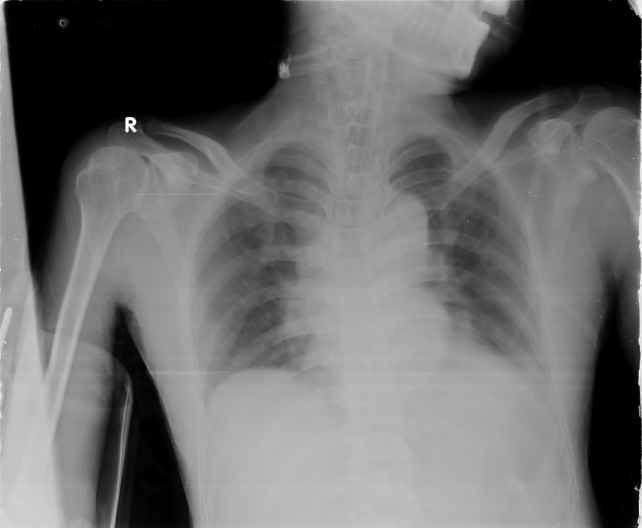

Chest x-ray